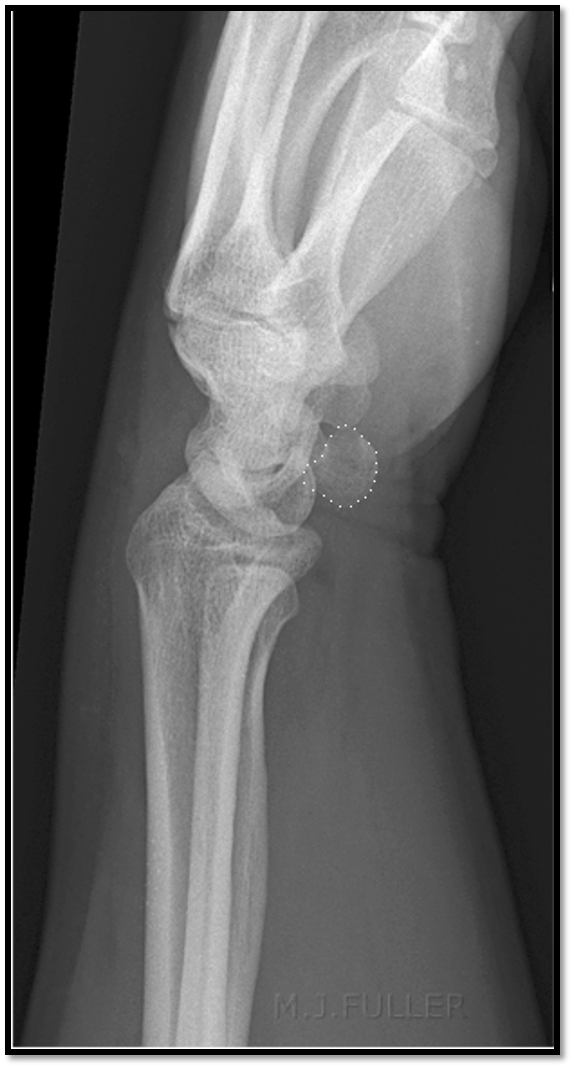

What is the positioning fault?

How would you fix it?

A

• scapholunate joint is closed (obliqued)

• trapezoid and trapezium are seperated